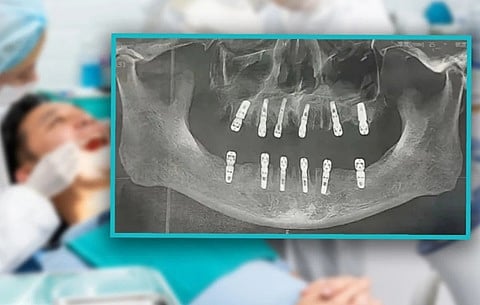

ذكرت تقارير أن رجلاً صينيًّا خضع لخلع 23 سنًّا، وتركيب 12 سنًّا أخرى، خلال عملية جراحية واحدة مستمرة، وتوفي بعد أسبوعين بسبب نوبة قلبية.

ويُظهر نموذج موافقة "هوانغ" على الجراحة أن أضراسه تم غرسها في اليوم نفسه الذي تم خلعها فيه، وهو ما يتعارض مع البروتوكول الطبي المعتاد.

وقال شيانغ غولين، رئيس مركز طب الأسنان في مستشفى ووهان الرابع: إنه من غير المعتاد أن تستخرج عملية جراحية واحدة 23 سنًّا في إجراء واحد، بينما من المعتاد ألا يتم استخراج أكثر من 10 إلى 12 سنًّا.